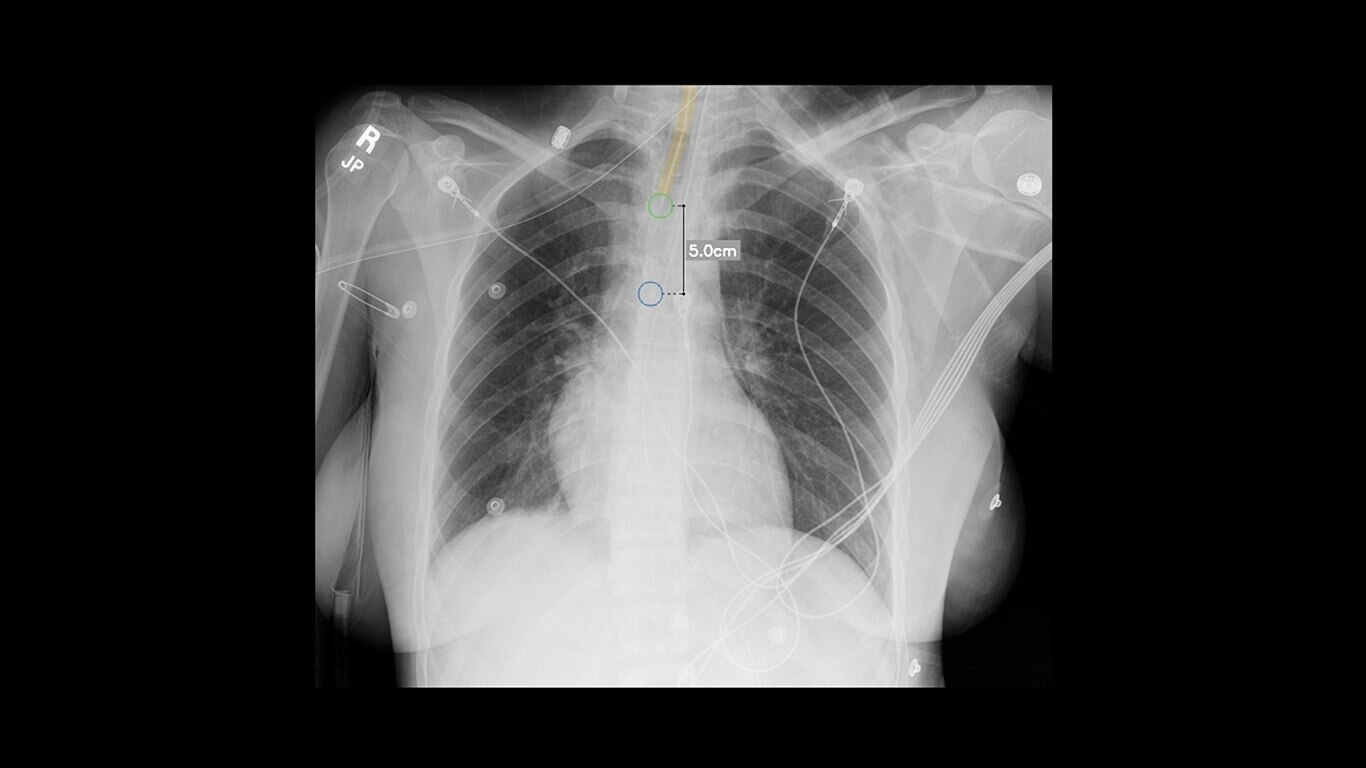

On-device AI

Automatically identifies critical conditions and provides onscreen quality checks